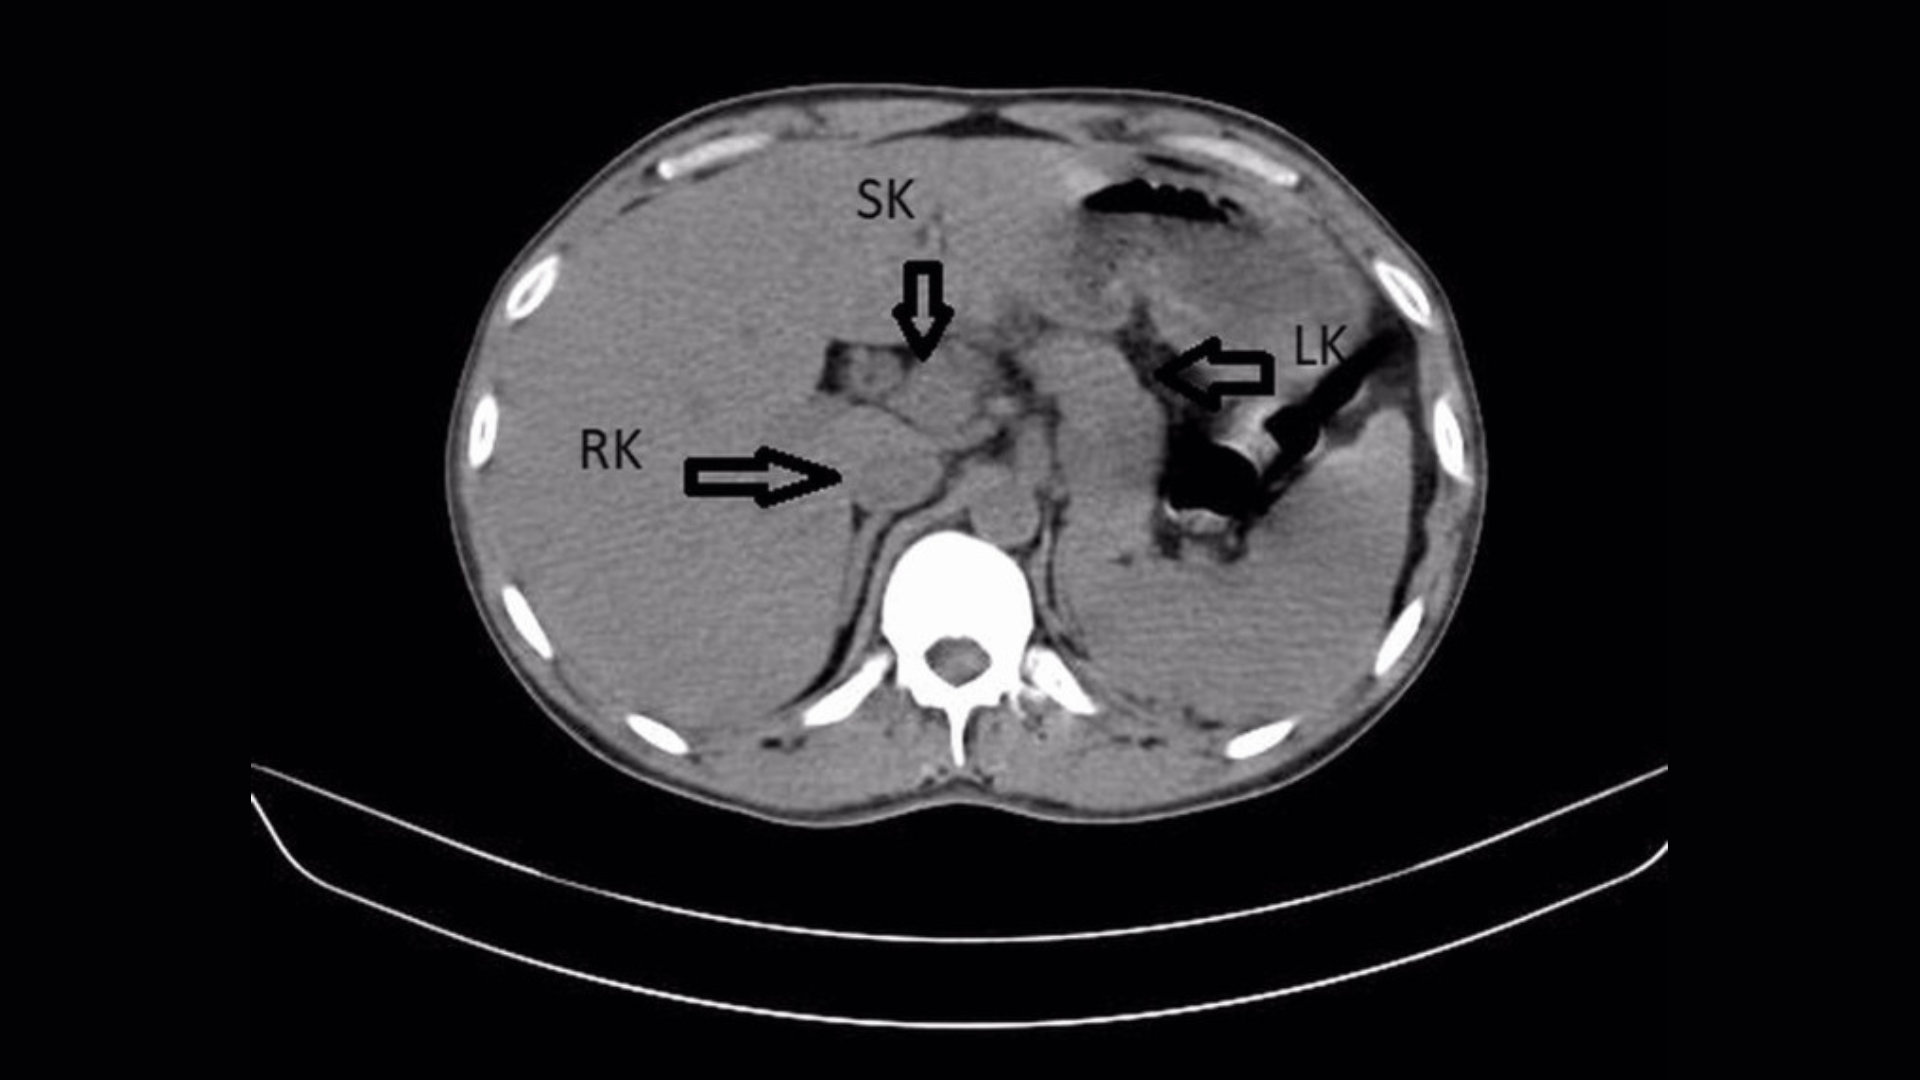

But in addition, an ultrasound and a CT scan of the patient’s abdomen revealed something unexpected: a third kidney, also known as a supernumerary kidney. It was fused to the man’s right kidney, creating a horseshoe shape.

A supernumerary kidney is a congenital anomaly that is thought to emerge during fetal development. It appears due to abnormal cell division in the cord that later forms the kidneys. A supernumerary kidney can sometimes lead to kidney infections, but the condition does not always affect normal kidney function and often goes undetected, according to the report.

In this case, the patient’s left and right kidneys were swollen and showed accumulations of calculus, or mineral crystals. These hard crystals form when urine is more concentrated; small “stones” often pass normally during urination, but can lead to infection if they linger untreated in the kidneys.

A fused “horseshoe” appearance with another kidney is even rarer, with only five cases reported in the scientific literature. Third kidneys can also be completely separate or loosely connected to another kidney by a thin layer of tissue.